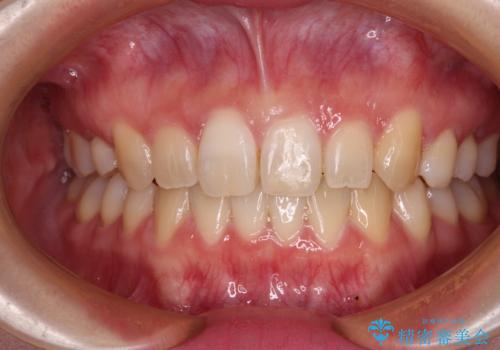

ディープバイトをインビザライン矯正で改善

前歯のインプラント治療 折角なので矯正治療できれいな歯並びに

八重歯を抜歯矯正でスッキリと メタルブラケットでの矯正治療

前歯のクロスバイト ワイヤー装置を併用したインビザライン矯正

八重歯と開咬を治したい 目立たないハーフリンガル矯正

前歯のクロスバイトを短期間で解消 目立たないワイヤー矯正

前歯のがたつき 部分矯正でコストダウンしながら、かみ合わせも治療

【引っ込んだ前歯が気になる、真ん中の線も揃えたい】インビザライン症例

【出っ歯が気になる】インビザライン症例

【前歯のガタガタが気になる】インビザライン症例

八重歯で口元が膨れている ワイヤー装置での抜歯矯正

【モニター】飛び出した上顎前歯のワイヤー矯正で改善

前歯が反対に咬んでいる インビザラインによる矯正治療

重度のガタガタと出っ歯をワイヤーによる抜歯矯正で整った歯並びへ

八重歯をインビザラインで非抜歯矯正